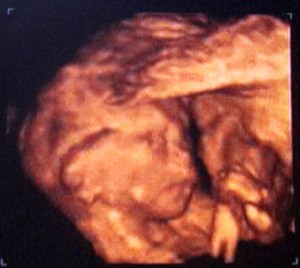

Tenemos suerte y la ginecóloga es un encanto y para más inri, cachonda. Nos pregunta si sabemos y queremos saber el sexo del bebé, y al unísono mi chico y yo decimos que sí. Me enchufa el gel helado ese en la barriga, y tal cual pone el cacharro sobre la masa transparente, zasss!! las cosotas de nuestro bebé on the air!!

«¡Menudo chavalote!. Ahí lo tenéis, ¿Lo veis? Bien dotado el chaval» nos dice «¡No para de moverse! Qué energía!«. Mi chico y yo nos miramos, ¡¡Es niño!! qué fuerte… y menuda huevada que se gasta, jajajaja. Nos echamos unas risas a costa del pequeño, angelico… No me lo tengas en cuenta, hijo, tu padre y yo somos asín, del caca-culo-pedo-pis

Todo está perfecto, todo esta bien. La tía se lo curra y nos quiere mostrar la carita del peque, que está contra mi bajo vientre y el tío tímido no se quiere mostrar por más que la doctora da pequeños golpes con el cacharro ese untado en gel en mi vientre a ver si se gira. Como siga así me meo encima. Pero nada, no hay forma. Parece que el peque dijera: «anda iros a tomar por culo, dejadme en paz, cagüentó…».

Me hace girarme sobre un lado, lo intenta y nada. Me pide que me gire al otro lado rápido, así lo hago y ¡¡se le ve la carita!! Más bien cara de «Qué ha pasao??!!» del susto que se lleva el pobrecito mío… Es una pasada… Mi chico y yo mirábamos ambas pantallas embelesados y flipados… Aaaains…